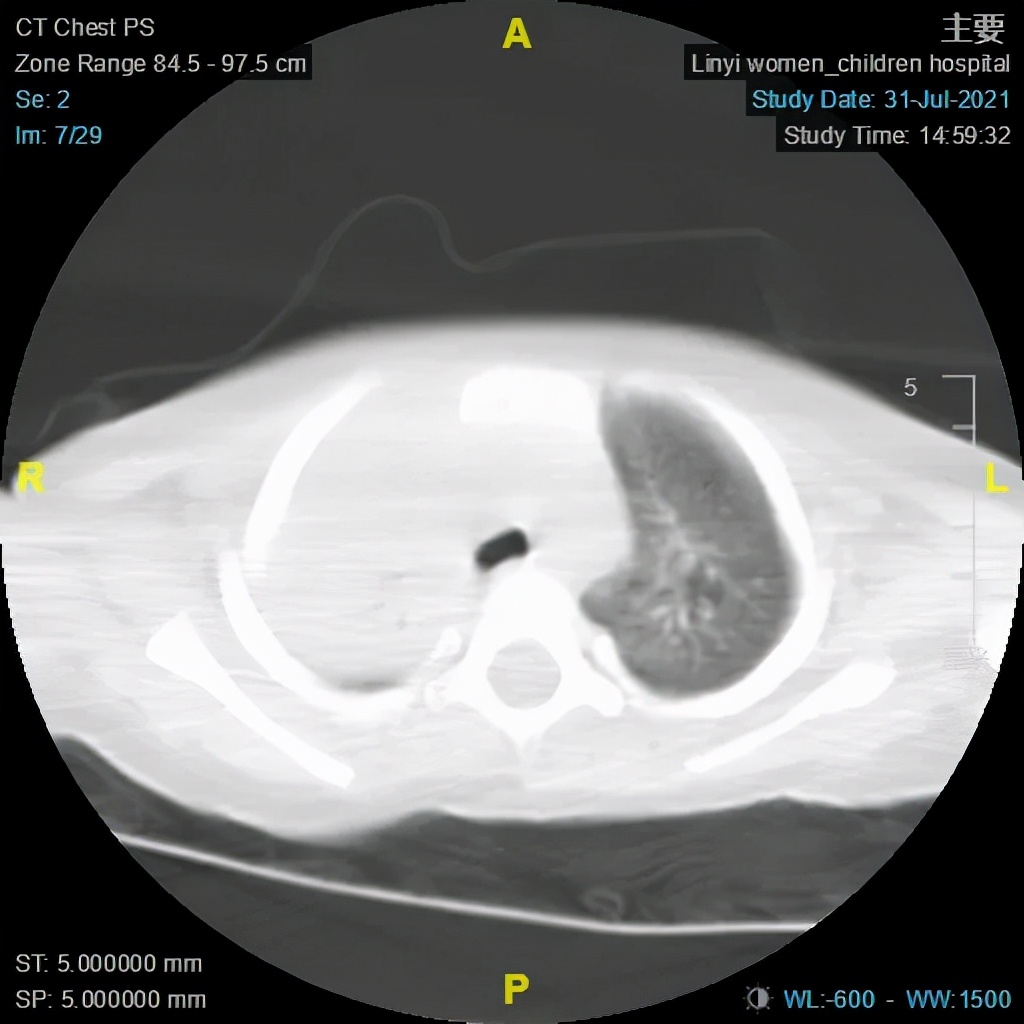

大叶性肺炎术前及术后CT对比图

(电子支气管镜、支气管肺泡灌洗术术前)